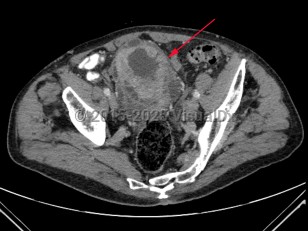

Metastatic pancreatic carcinomaMetastatic pancreatic carcinoma

Abdominal aortic aneurysmAbdominal aortic aneurysm

Ovarian cancerOvarian cancer